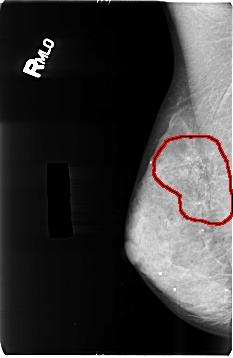

FILE: B_3496_1.RIGHT_MLO.OVERLAY

TOTAL_ABNORMALITIES 1

ABNORMALITY 1

LESION_TYPE CALCIFICATION TYPE PUNCTATE-AMORPHOUS DISTRIBUTION REGIONAL

ASSESSMENT 4

SUBTLETY 4

PATHOLOGY BENIGN

TOTAL_OUTLINES 1

BOUNDARY